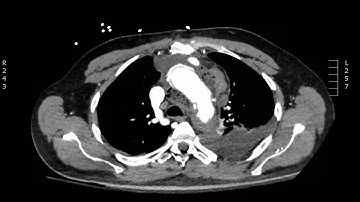

Cobweb sign in aortic dissection